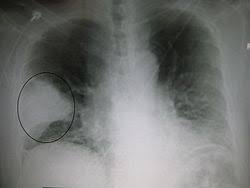

التهاب الرئتين من الأمراض الشائعة

المصاحبة لقدوم البرد حيث يصاب الآلاف بهذا المرض الذي كان قاتلا فيما مضى، ولكن رغم تحسن اكتشافات المضادات الحيوية فإن كثيرين ما زالوا يضطرون لدخول المستشفى للعلاج منه.

التهاب الرئة مرض مزمن سببه غالبا البكتيريا، وفي حالات غير شائعة قد تسبب الفطريات أو الفيروسات هذا المرض، أو بعض المواد السامة أو الأجسام الغريبة التي تدخل إلى الجهاز التنفسي وتؤدي إلى التهابه، كما أنه قد يصيب الأطفال الرضع بسبب بكتيريا "العنقوديات الذهبية".